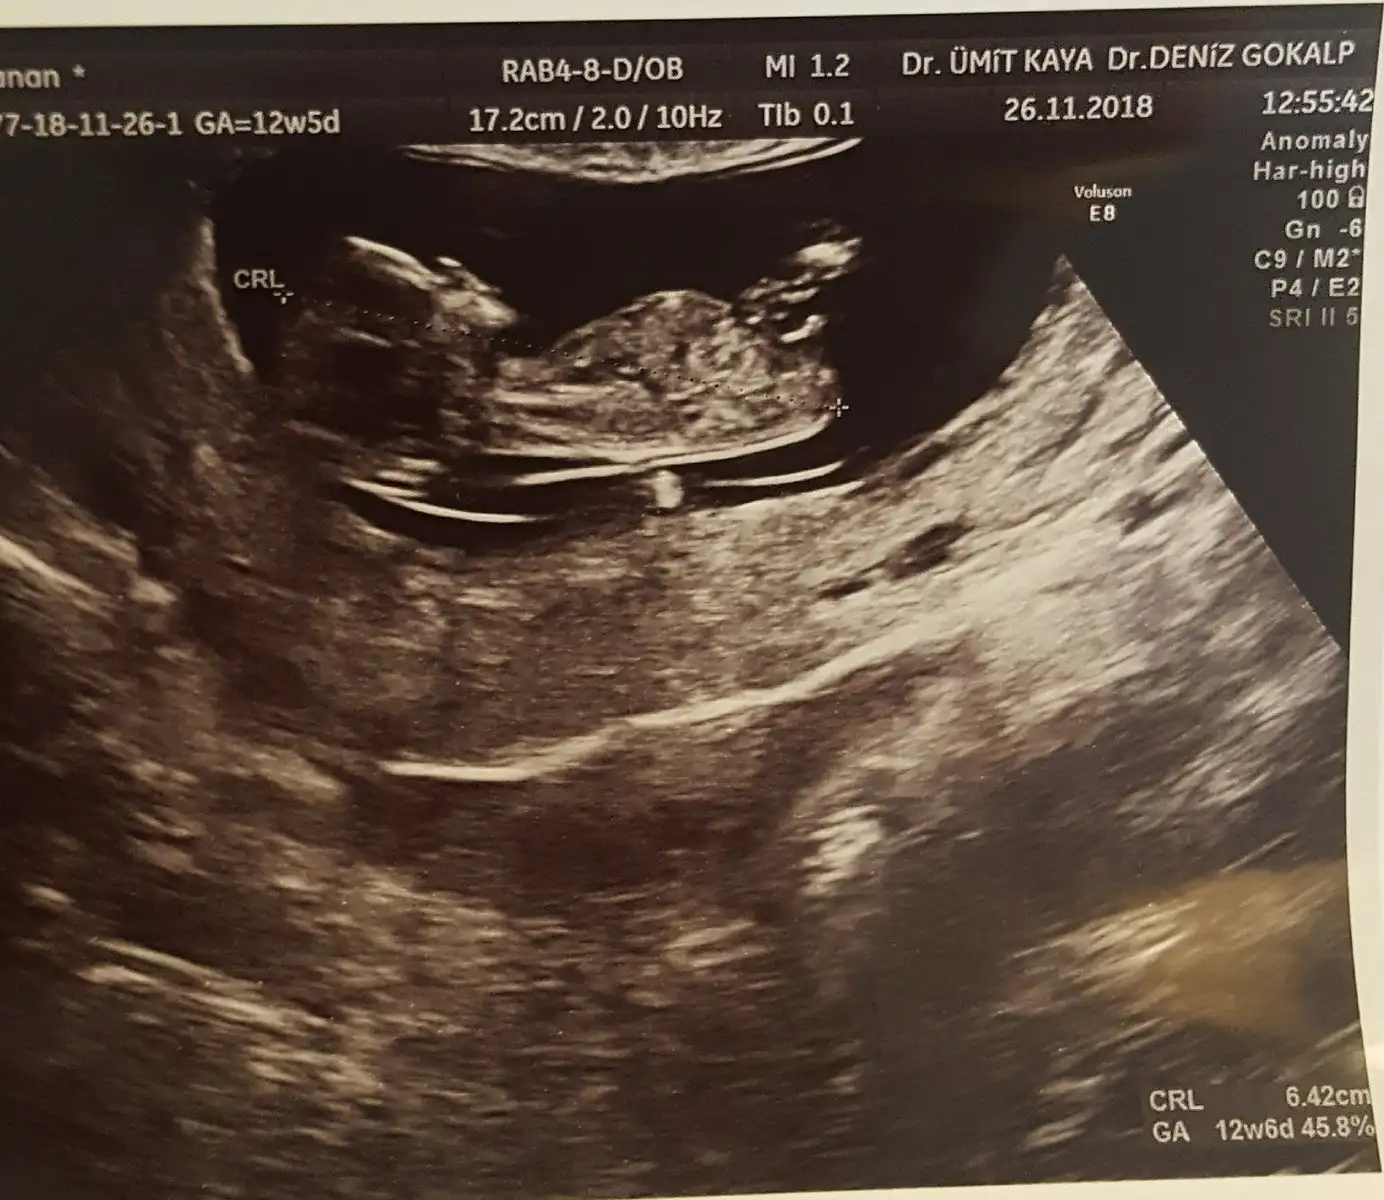

görülüyormuşum sevindim evet küçük biraz ben kafasını bile anlayamadım

çok yazıldığı için arada kaynayabiliyor. Ben nub fotoğrafını 2 kere attım mesela. Peki bununla sınırlı kalacak mıyım ?? :KK70: hayıııırr.. herkes yazana kadar atıcam:KK75: